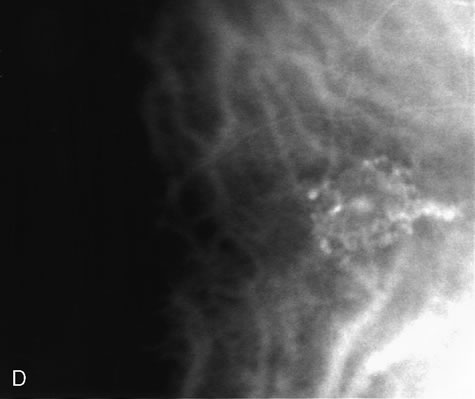

FA is also useful in characterizing two other subgroups of CNV: retinal angiomatous proliferation (RAP)8–16 and polypoidal choroidal vasculopathy (PCV).17–50 RAP begins in the deep retinal complex, forming intraretinal neovascularization (IRN), which may subsequently progress to extend beneath the neurosensory retina, forming subretinal neovascularization (SRN), and a vascularized PED.8 In the later phases of the process there may be a retinal-choroidal anastomosis (RCA). Clinical features of RAP include intraretinal hemorrhages, cystoid macular edema, and associated vascularized PED. FA is useful in revealing the presence of the angiomatous intraretinal vascular complex and the extension of the associated PED (Figs. 12 and 13). However, other diagnostic techniques such as indocyanine green (ICG) angiography, and optical coherence tomography (OCT) may be able to better demonstrate the presence of the RAP lesion.

PCV is characterized by the presence of dilated, choroidal vascular channels ending in orange bulging polyp-like dilations in the peripapillary and macular area. Associated features are recurrent subretinal hemorrhage and vitreous hemorrhage, relatively minimal fibrous scarring, absence of retinal vascular disease, pathologic myopia, and signs of intraocular inflammation. FA demonstrates the presence of the dilated vascular channel (Fig. 14 and 15). However, the presence of blood and exudation may block the details of the choroidal circulation on the angiogram. In these cases, ICG angiography can better demonstrate the presence of a distinct network of vessels within the choroid because the larger choroidal vessels are filled with dye.